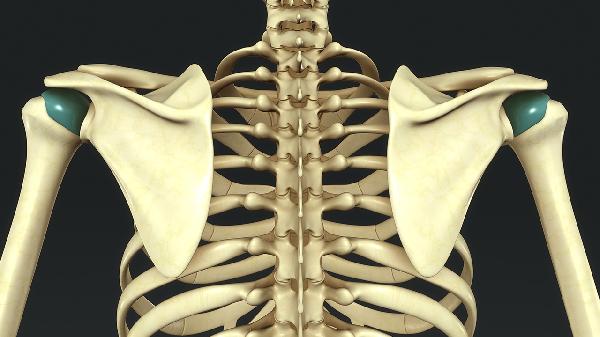

胚胎期椎体分节障碍导致半椎体、蝴蝶椎等结构异常。新生儿期可通过MRI确诊,20度以内畸形建议观察,40度以上需考虑后路脊柱融合术,术中采用椎弓根螺钉系统固定。